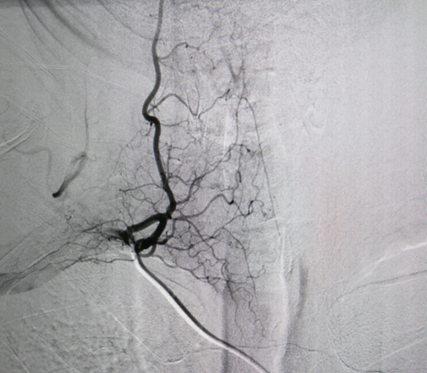

12月20日,湘雅常德医院放射介入科成功实施了第一台脑部及脊髓数字减影血管造影(DSA)手术。 常德南坪镇的56岁患者肖大叔,因阵发性背痛持续7天,后加重伴左侧肢体乏力于外院行CT、磁共振等检查,被怀...